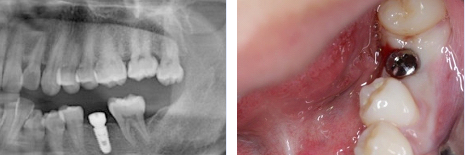

种植术后全景片、即时照片